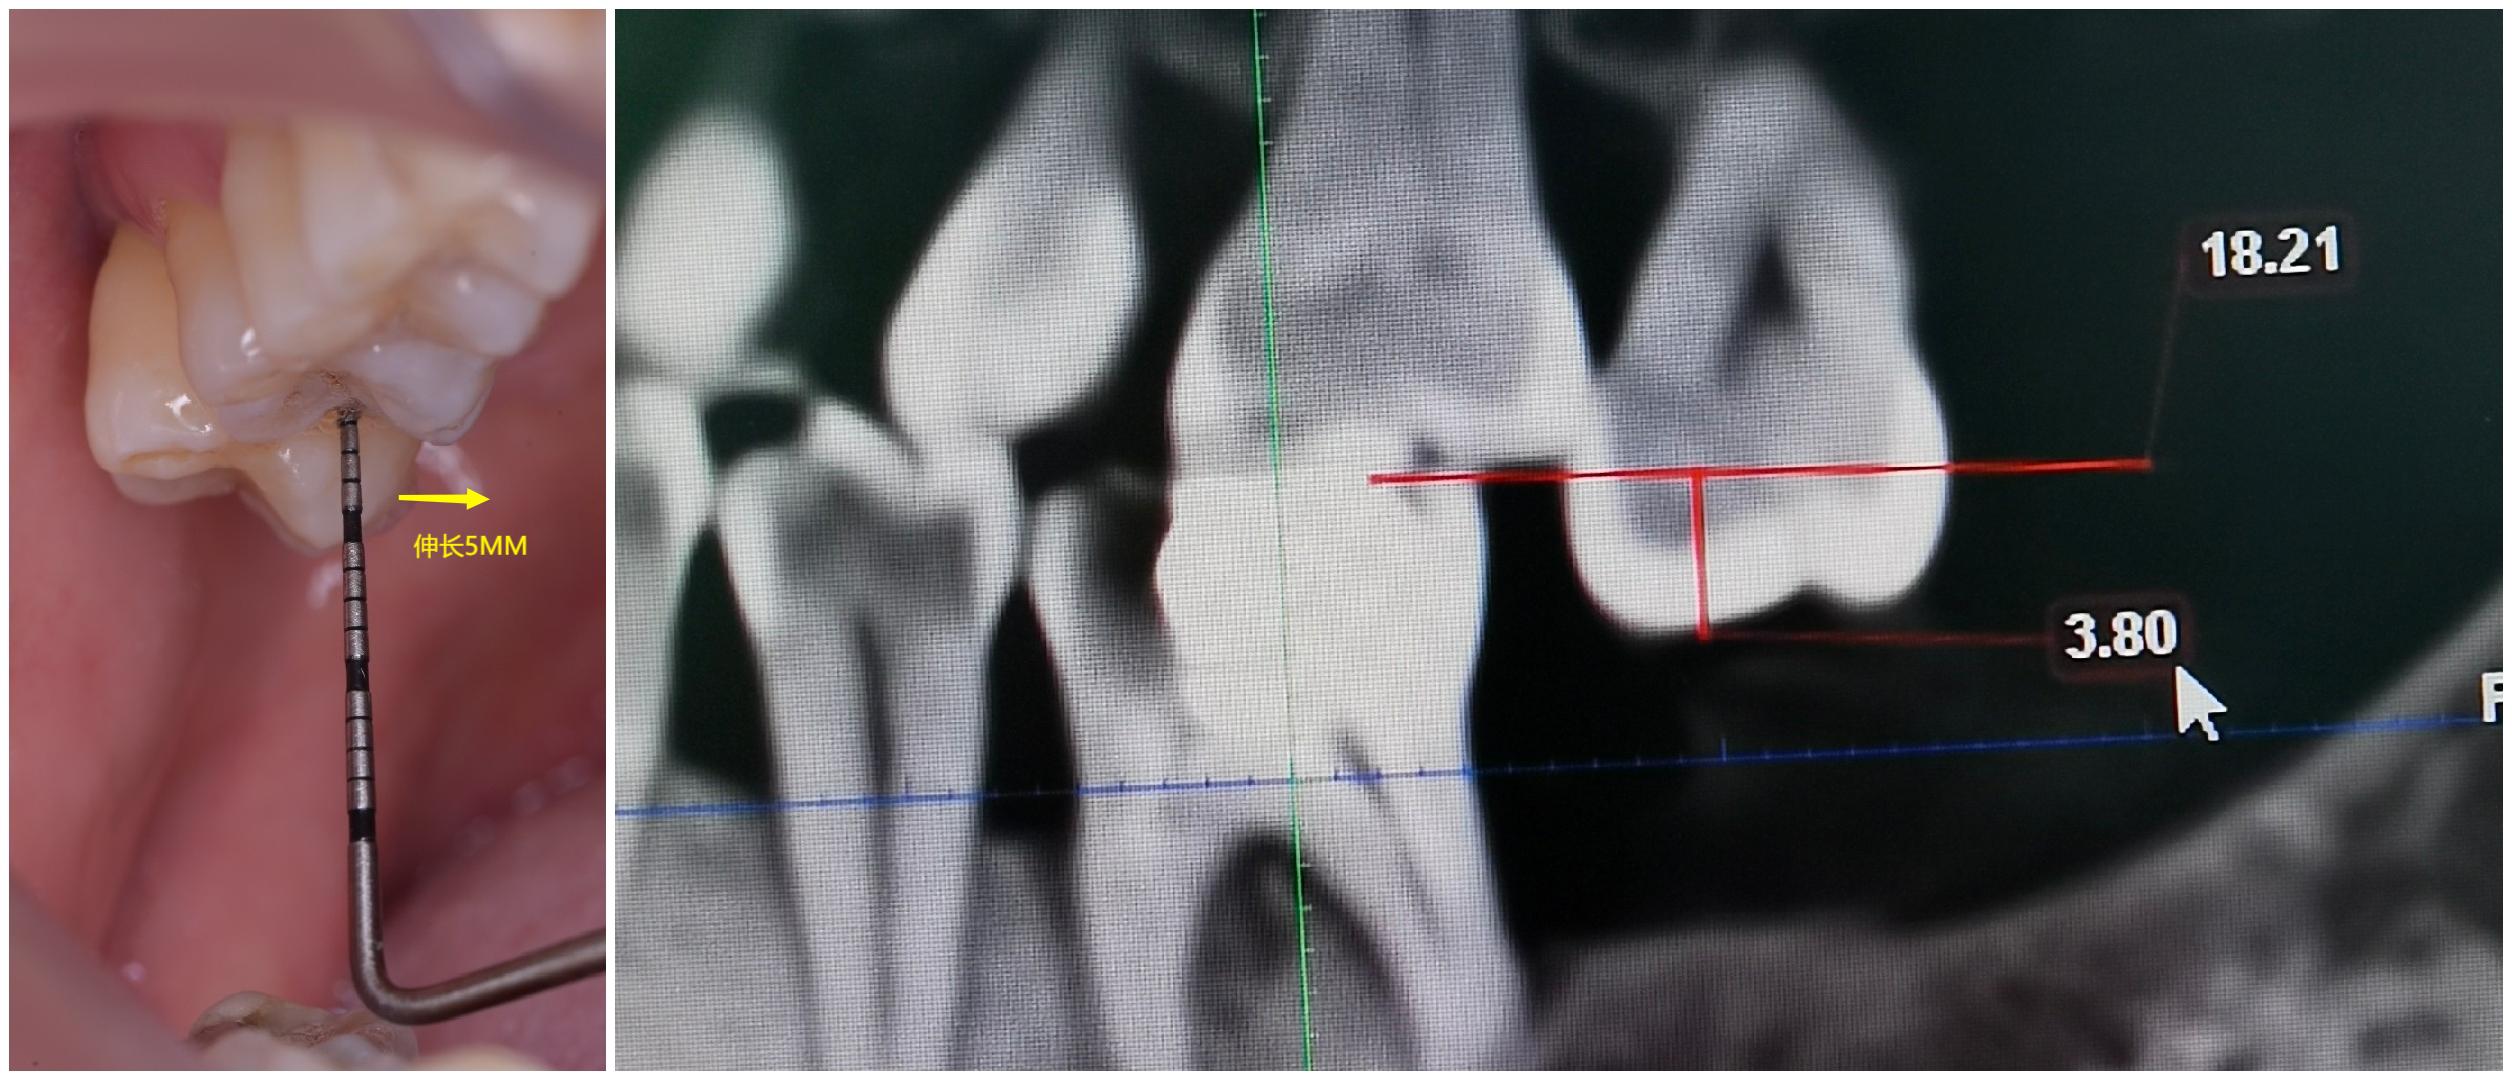

3、阻生智齿

长智齿的时候前面牙会受到压力邻牙或门牙有会被顶歪的可能